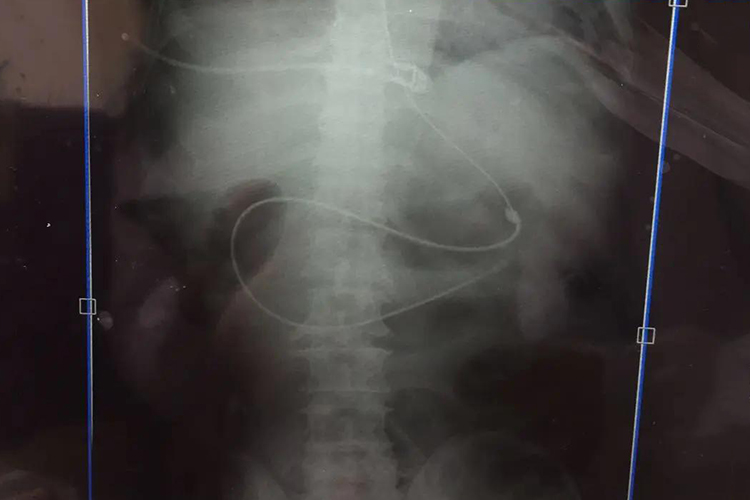

先以常规的放置胃管的方法将鼻空肠管放置入胃内,并继续缓慢推进,当有落空感时说明通过幽门,再逐步用力推进,当置管深度在110-120cm时会到达屈氏韧带,回抽有金黄色肠液说明已经到达。一般手法置管后需要进行床旁X线腹部平片检查。